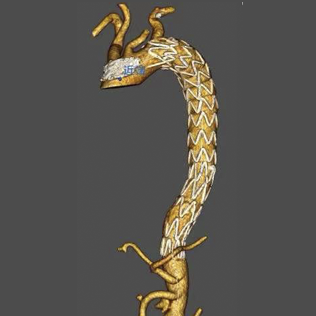

Talos™ Thoracic Stent Graft System is indicated for the treatment of Stanford type B aortic dissection, and can improve the reshaping of the distal true lumen by extending the stent length.